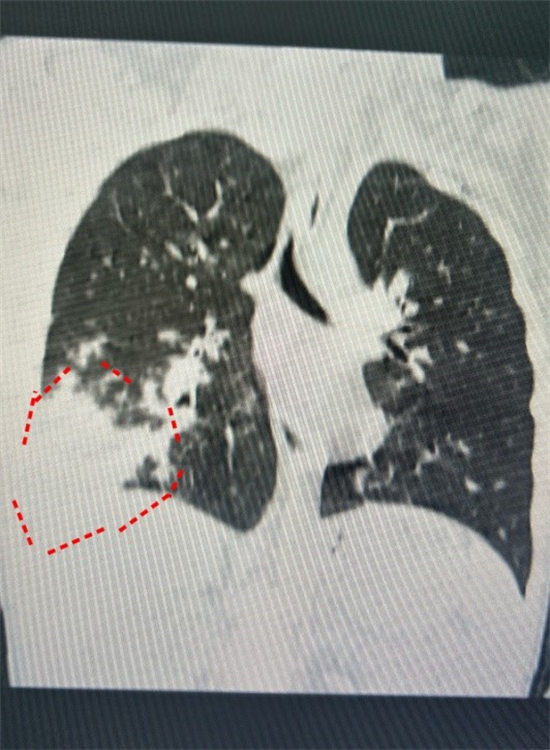

就在几天前,有个7岁的男孩子悠悠(化名),因为由于久咳不愈发生了气喘来到了儿科诊室。接诊的郑绪阳询问后才得知,原来在三个多星期前,悠悠发过三天高烧,当时爸爸妈妈跟以前一样,给他服用了家里常备的抗生素和退烧药。三天后悠悠退烧了,退烧后却一直咳嗽,越咳越厉害,这才来到医院。经过胸部CT检查,发现他的左肺已经白掉了一大块。之后的化验结果证实,悠悠患上了支原体肺炎,马上被收治入院。

以往大家印象中,得了肺炎会发高烧,但郑绪阳说,近年来,不典型症状的肺炎越来越多,很多肺炎患儿血象不高,咳嗽也不厉害,发现久咳不愈出现气喘才来检查,结果肺部CT一检查,发现肺已经白掉了一大块。